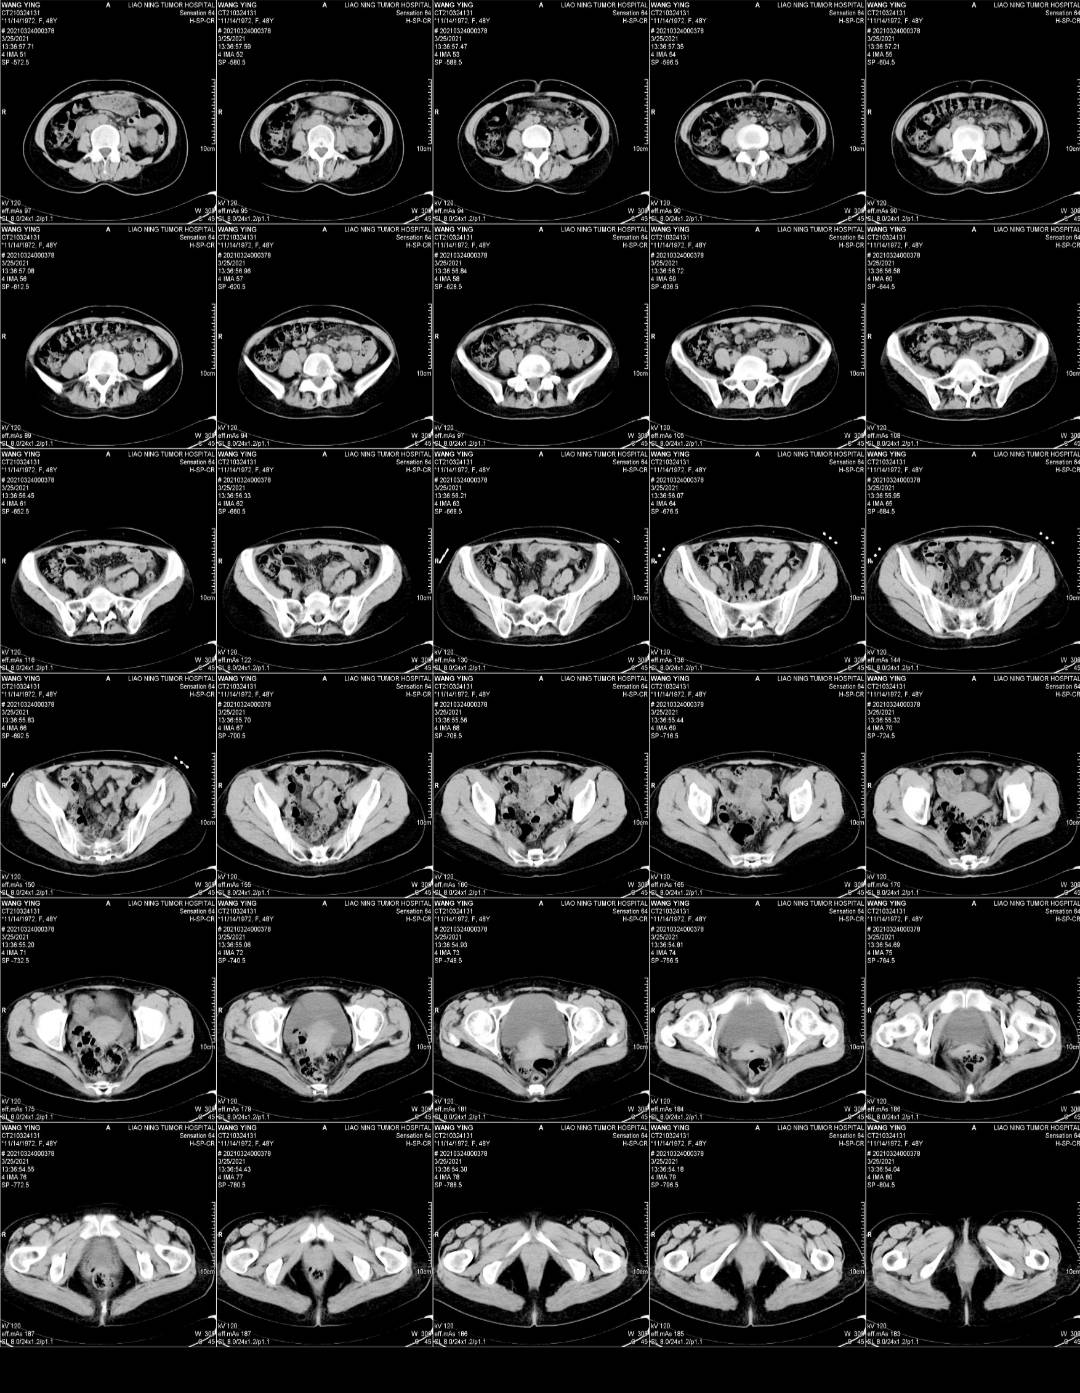

3.24吃一个月凯美纳 复查,打唑来膦酸第二针,当天看到血的结果就觉得不对劲,一些指标还在升高,就跟医生联系,她也觉得不对劲,说等ct再看看。

25号下午做的ct,当天晚上我就在手机上看到了报告,没写大小,感觉不妙,心里非常慌。

今天早上让爸爸取完ct就发给我,真的是没有好转。

下周一穿刺取病理,看看有可能是小细胞吗?